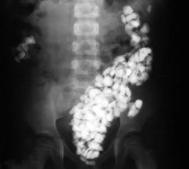

b. X-ray to identify what was eaten and detect blockages in the intestines if any.